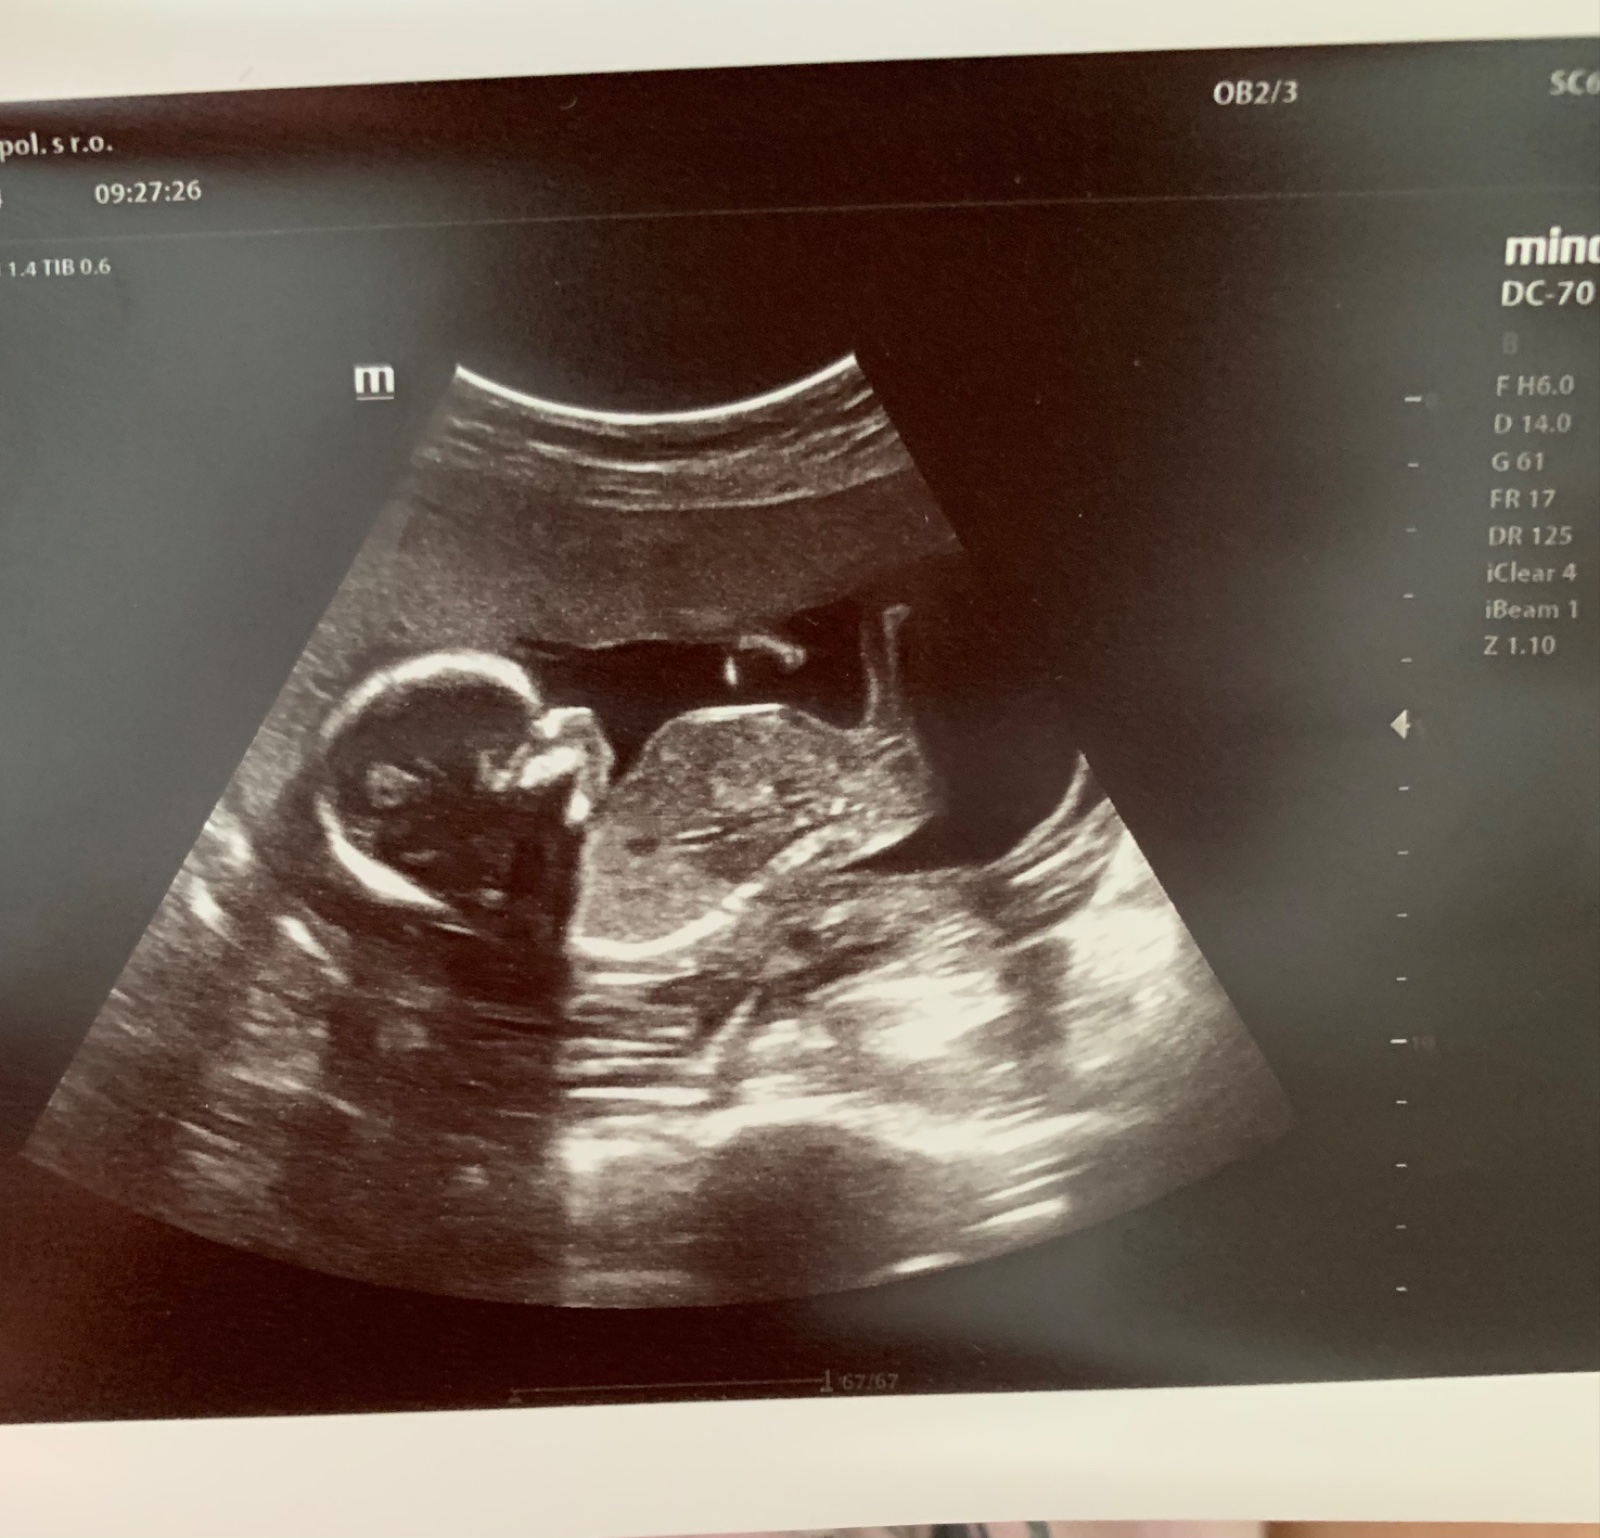

Ano fotka nie je pri dobrej polohe takze zbytocne tu polemizovat, nevidiet na nej nic viac, nez to co videla dr pri vysetreni 🙂

Ako sa zisťuje pohlavie dieťaťa?